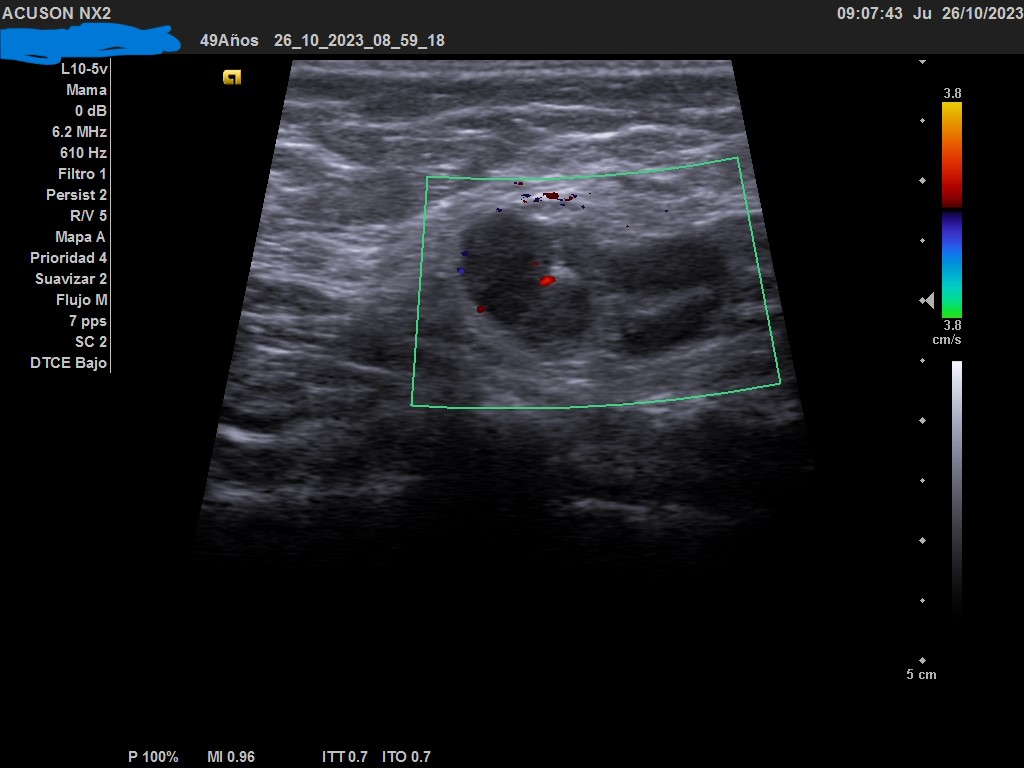

Hallazgos ecográficos

Ecografía: mama izquierda se observa tumoración hipoecogénica lobulada en cuadrante superior externo de aproximadamente 4 cm, heterogénea, que capta al Doppler color y dos adenopatías de aspecto reactivo en axila homolateral. Imagen sospechosa de malignidad.